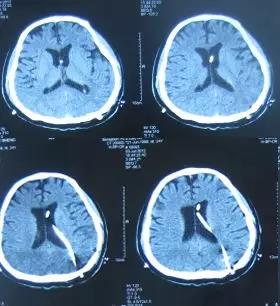

患者于2003年3月1日即15岁时,突发头痛,疼痛难忍,就诊于山东省菏泽市某医院,头部MRI检查诊断为“脑积水”(片子丢失),经保守治疗后症状仍无改善,于2003年4月20日进行了第1次右侧脑室-腹腔分流术,术后6天即2003年4月26日,头痛基本消失,复查头部CT:一侧脑室缩小(图-1),随后出院。

图-1:2003年4月26日头部CT